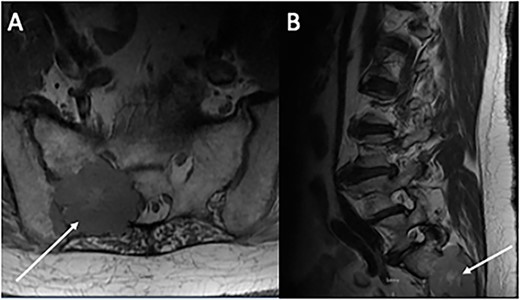

A total of 6 weeks after surgery, while preparing for postoperative radioactive iodine therapy (RAI), the patient developed right hip pain and leg numbness. MRI of the lumbar spine revealed a 5.0 × 4.6 cm expansile lesion in the right sacroiliac joint (SI) and a herniated disk at L3-L4 (Fig. 3). CT-guided core biopsy of the mass confirmed metastatic PTC. He was treated with 165 mCi of I-131 and subsequent whole-body scan (WBS) showed uptake in the neck, right SI joint, and the posterior mediastinum. A positron emission tomography (PET-CT) scan demonstrated 18F-fluorodeoxyglucose (FDG)-avid mediastinal and left hilar adenopathy with no residual disease in the head and neck (Fig. 4). The patient was then treated with external beam radiation therapy with 40 Gy to the sacrum in 20 fractions. He was started on zoledronic acid, dabrafenib, and trametinib, but later switched to lenvatinib when follow up imaging showed persistent metastases. At 36 months following surgery, the patient remains on lenvatinib with PET-CT evidence of new peritoneal carcinomatosis and stable osseous metastases.

Magnetic resonance imaging of the lumbar spine. (A) Axial and (B) sagittal sections demonstrating an expansive 5 × 4 cm lesion in R sacroiliac joint. CT-guided core biopsy of the mass confirmed metastatic PTC.